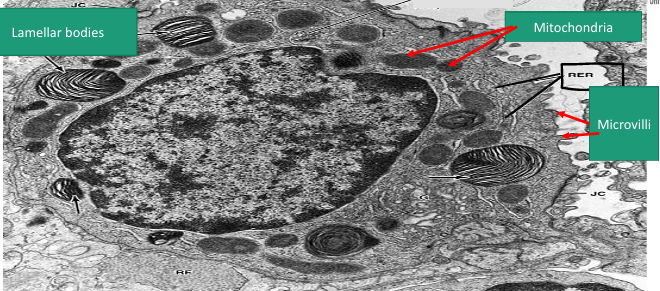

Type II pneumocyte

A -Identify the cell

B -Identify the labelled structure

A- pneumocyte type II

B- Lamellar bodies